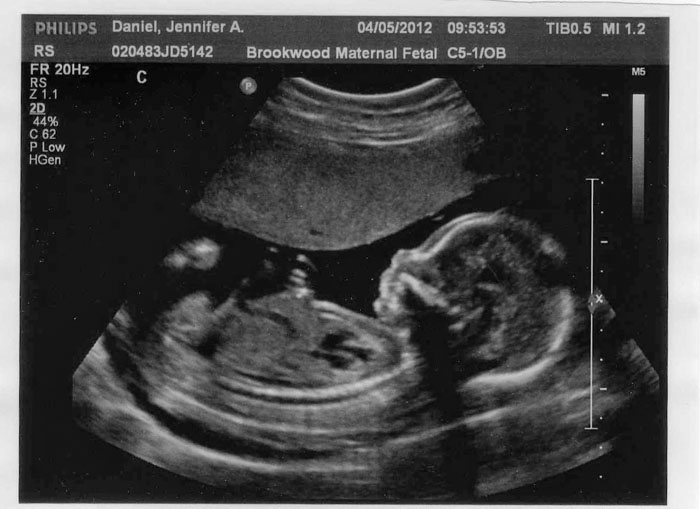

В 12 недель в среднем показатель равен 21 мм, на 16 неделе – около 34 мм, а на 32 – часто равняется 82 мм, в 40 недель – около 96 миллиметров. Бипариетальный размер не оценивается отдельно. Вместе с этим индексом вычисляют лобно-затылочный размер, который измеряется в одной плоскости с предыдущим показателем. Также БПР служит ориентиром в определении родоразрешения – ЕР или КС.

Давайте выясним, какие именно показатели могут присутствовать в протоколе УЗИ и каковы их нормы на сроке 30-34 недели. БПР. Речь идет о расстоянии от одного виска малыша до другого. В норме бипариентальный размер составляет от 6,7 до 9,1 см (в среднем от 7,5 до 8,3 см).